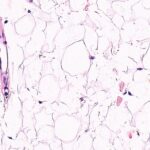

Hairy leukoplakia (HL) is a histological manifestation of HIV infection and is distinguished by parakeratosis of the oral mucosa, hyperkeratosis, keratinization of the epithelium, and numerous intracellular inclusion bodies made up of lipid vacuoles, concentric lamellar structures, and occasionally viral particles within macrophages.